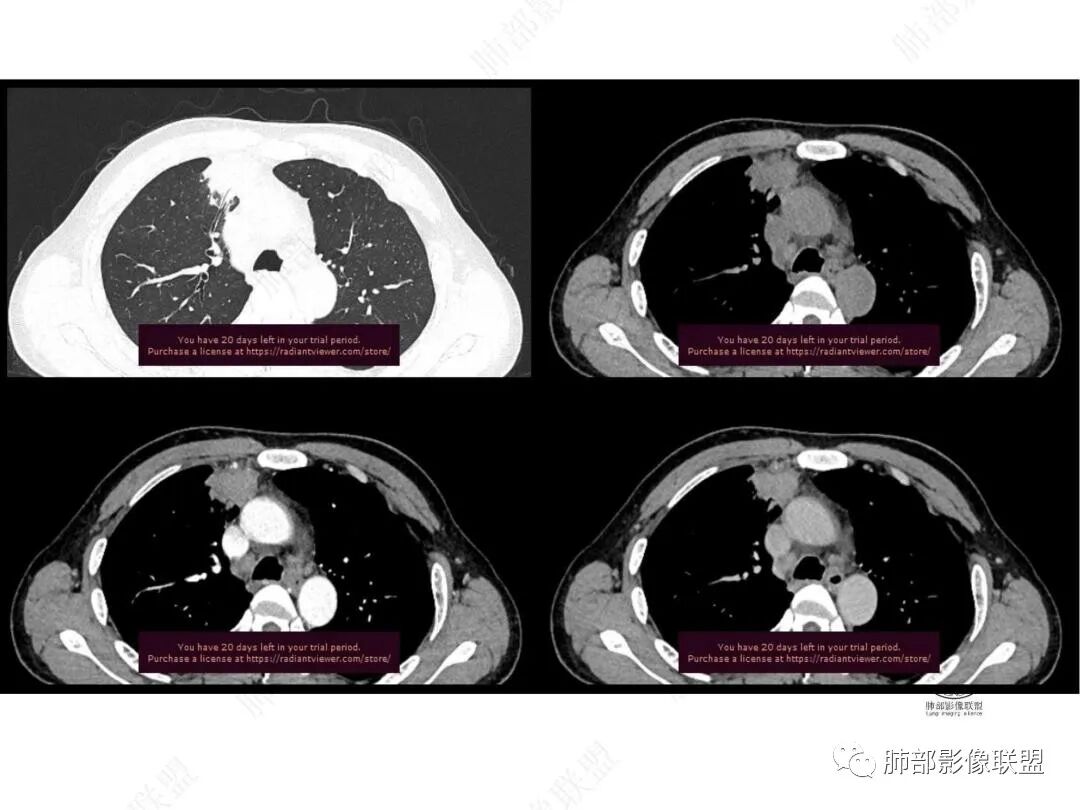

增强图像

CT值信息

中年男性,前纵膈旁团块,边缘平直,周围可见模糊的磨玻璃影,相邻支气管壁增厚,部分支气管进入病灶后阻塞,增强病灶渐进性强化,肝右叶见边缘不清的低密度影,增强渐进性强化。结合实验室检查,总体考虑炎性病变,自免性炎症?血管炎?

中年男性,右前纵隔旁不规则实变影,局部支气管进入后截断,病灶渐进性强化。肝脏右叶低密度灶,边界不清,呈明显渐进性强化。IMT?

男,49,低热3月。胸部CT:右肺上叶前段纵隔旁见团片影,部分边缘毛糙,部分平直、内收,邻近卫星灶、晕征,重建L征?支气管管壁增厚、进入后堵塞;纵隔可见肿大淋巴结;病灶密度较均匀,中度强化。肝脏片状低密度影,边缘模糊。考虑炎性病变,PC?TB?鉴别腺癌。

中年男性,反复低热3月伴近期乏力及右上腹隐痛,白细胞,中性粒及淀粉样蛋白A增高,PCT不高,IGA、IGg增高,类风湿因子增高,未提供IGg4水平,影像改变,左侧肋骨陈旧性骨折(2020年已存在)右上叶前段胸骨旁的胸膜下新发病灶,支气管进入后一段才堵塞,肺动脉进入,走行自然,未见破坏,明显均匀强化,气管及支气管壁有增厚,钙化,纵隔内淋巴结增大,均匀强化,无坏死,纵隔内脂肪混浊,局部强化,肝内低密度灶,延迟强化(肺内病灶,淋巴结、混浊脂肪,肝内病灶强化均一致,且均为延迟强化)。初步考虑:免疫相关性炎症,IGg4相关炎症可能大,依据:IGA、IGg增高(未提供IGg4,可能是故意隐藏了),类风湿因子增高,炎性指标增高,但PCT不高,细菌感染可能就变小,加上病变同时累及肺、纵隔淋巴结,纵隔内脂肪、肝。

肝脏病变明确,是轻度强化,延迟强化特点,边缘模糊,有轻微的包膜挛缩。

2.右肺上叶纵隔旁新发实性密度病灶,密度均匀,轻度强化,未见空洞、液化坏死及钙化,血管穿行自如,支气管进入后狭窄截止。灶周磨玻璃影边界不清,病灶未见明显分叶毛刺,平直、轻度收缩、周围偶见结节影,但未见树芽征。注意纵隔胸膜侵入或突入比较明确。纵隔淋巴结轻度增大。

4.肝脏病灶没有假包膜,没有动脉早期强化,没有肝硬化,未见扩张胆管,未见环形强化,也未显示靶征,缺乏肝细胞肝癌、胆管细胞癌、转移癌或肝脓肿特征。

但回顾性分析,如此少血供确实可以符合淋巴瘤,如果密度更均匀一点的话,这是我们有所忽略的地方。